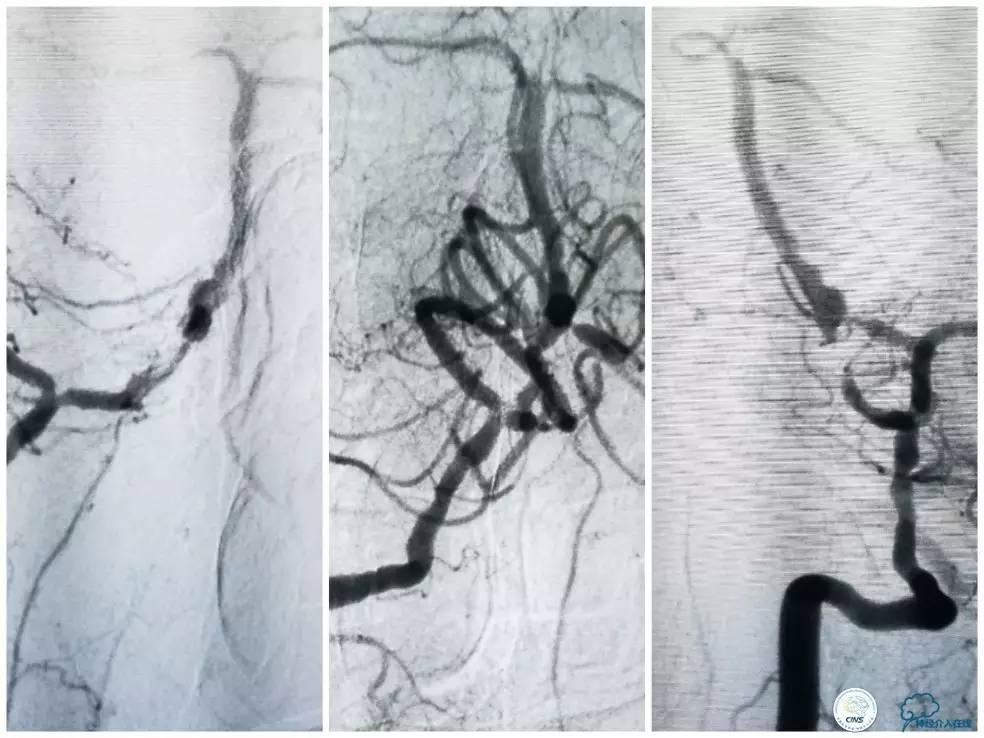

其后造影显示支架贴壁良好,远端血管显影好,前向血流TICI3级(图16)。

图16

缓慢回撤6F导引导管至锁骨下动脉,造影显示右椎V1段支架无移位,前向血流正常(图17)。

图17

1. 针对后循环合并颅内外串联病变处理序贯,目前尚无统一标准,各有利弊,如考虑近端狭窄程度较重且无明显迂曲的话,可以考虑先处理近端病变(详见第14期)。

2. 本例在近端支架释放完毕后,采用球囊辅助技术顺利的将导引导管越过支架。

3. 本例右椎动脉V4段至基底动脉释放支架后,有急性原位血栓形成,这与预扩张后残余狭窄率较高有关。选用稍大直径球囊后扩张,不仅改善了狭窄率,还将新形成的小血栓机械粉碎。但在椎基底交界区后扩张要考虑有潜在血管破裂风险。